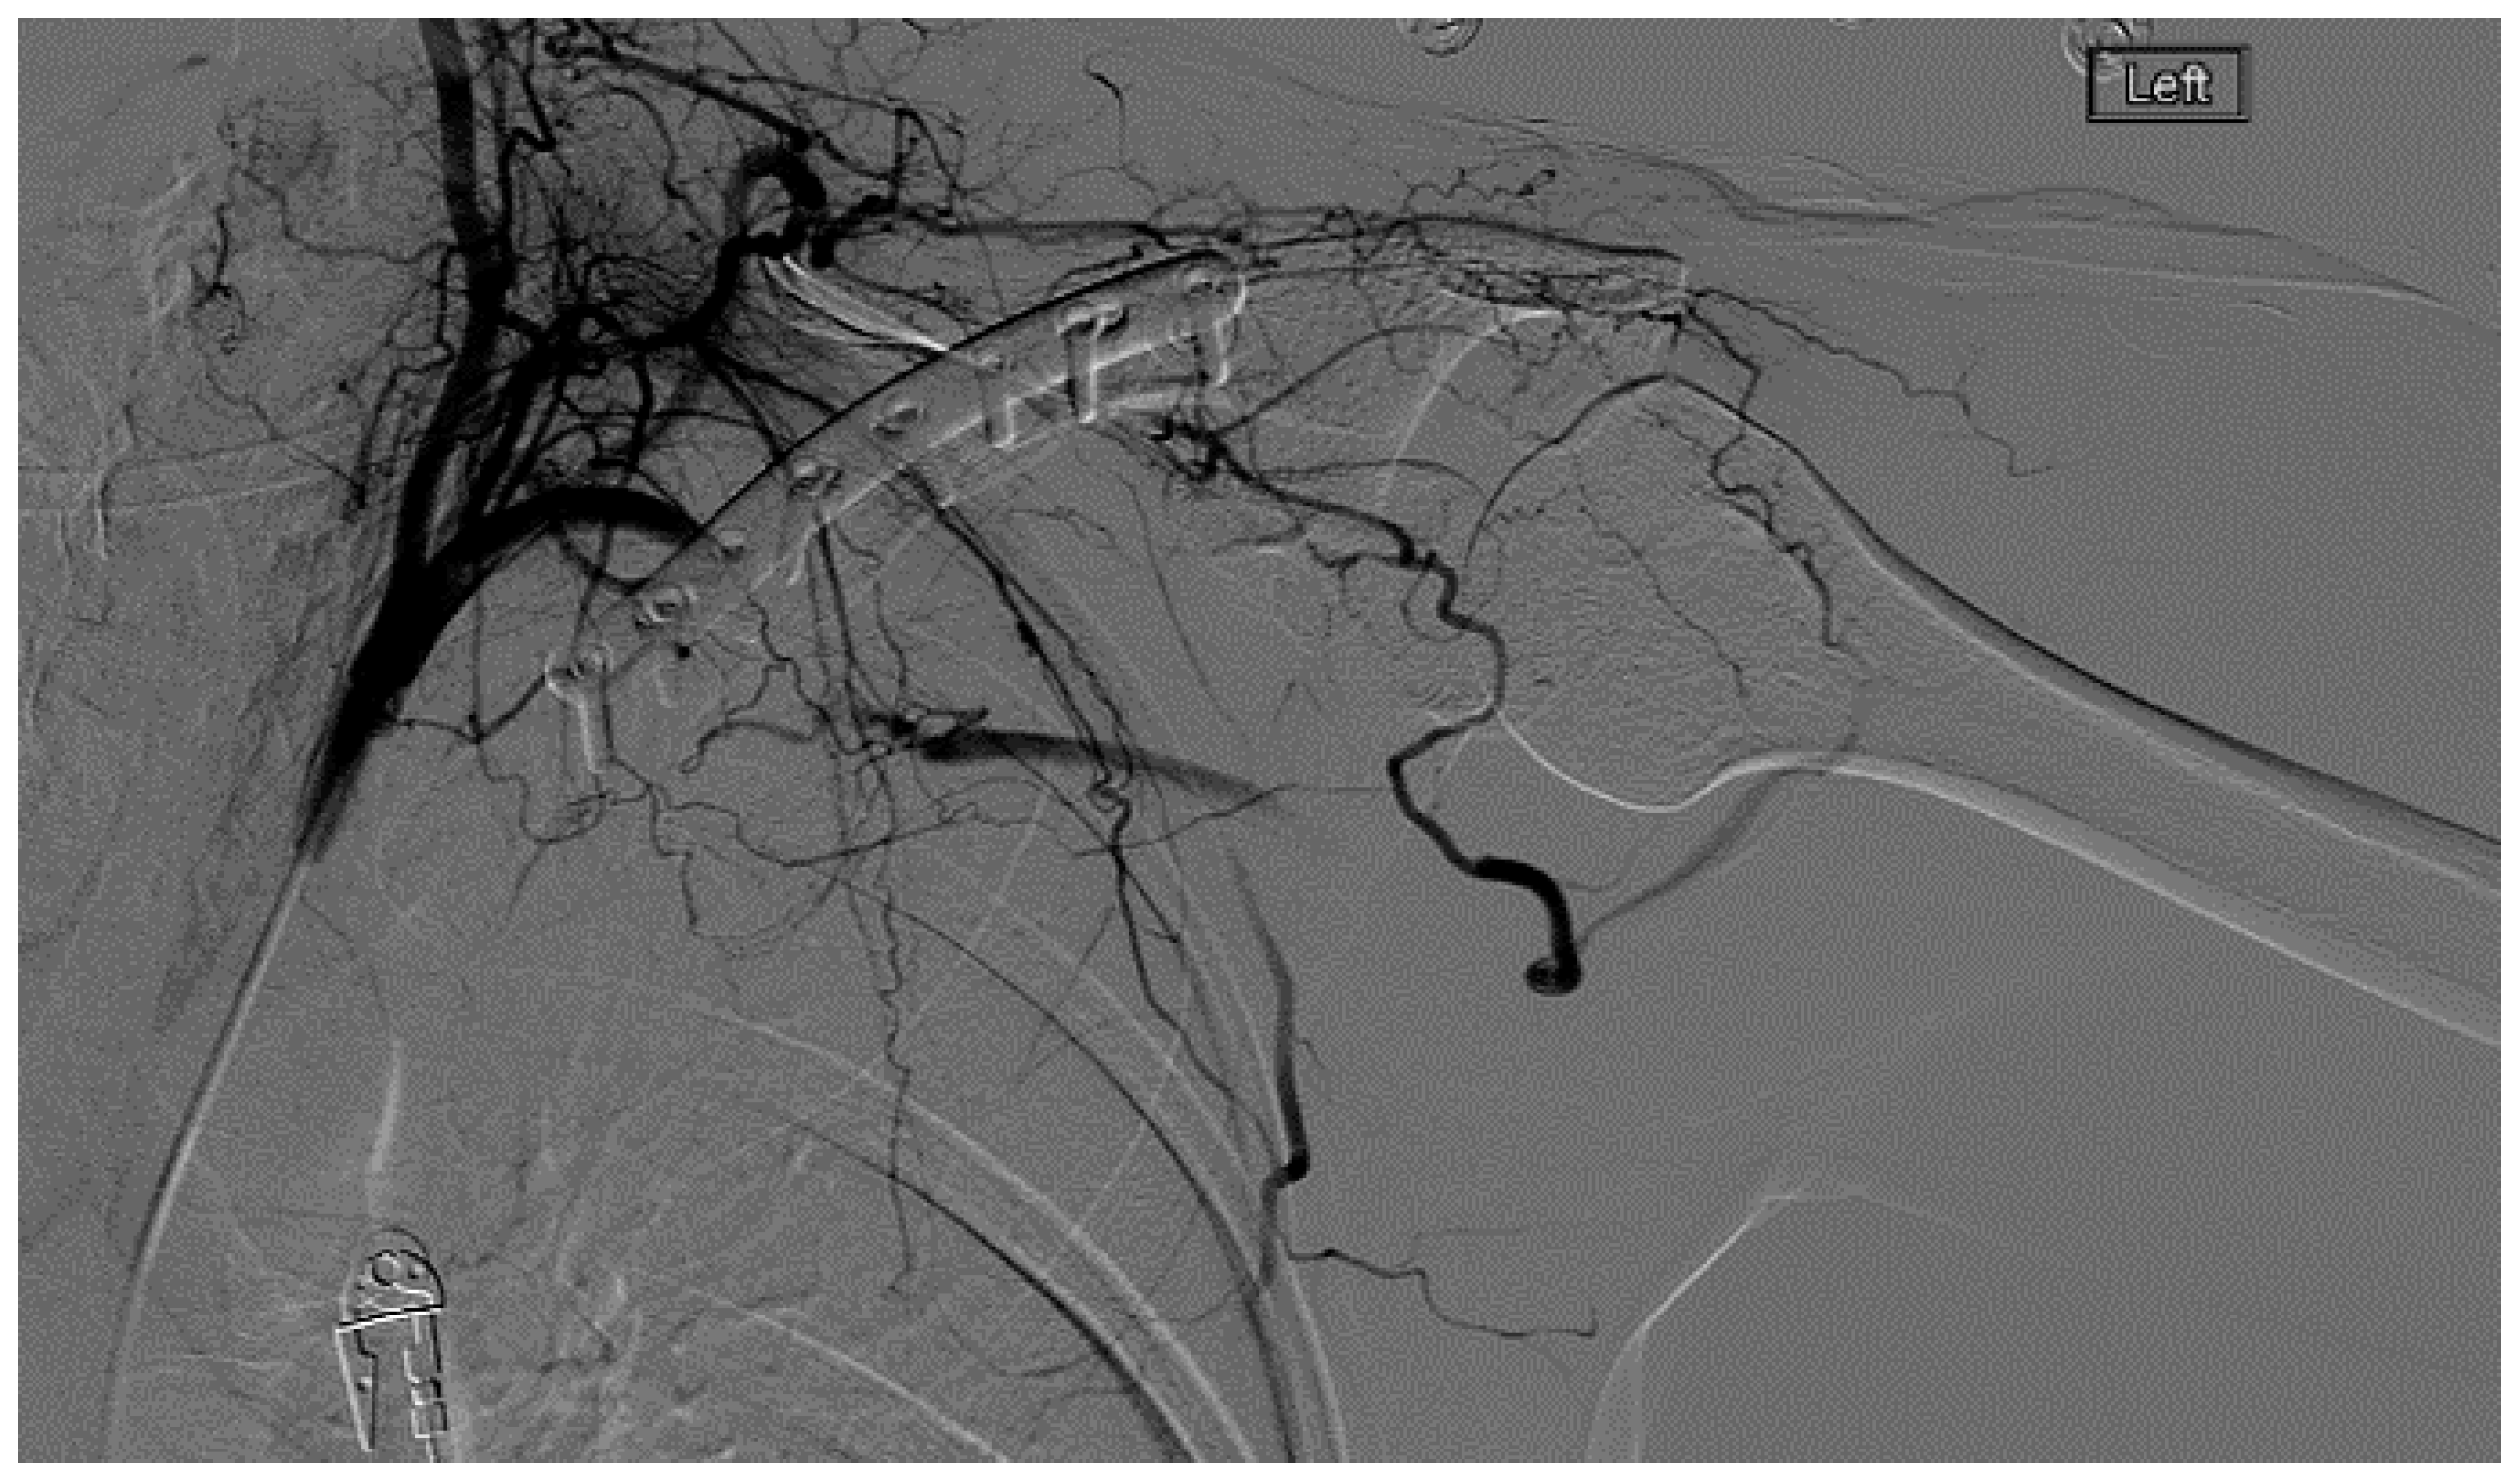

A heparin drip was then initiated, and she was taken to the catheterization lab for thrombolysis. This was carried out with Alteplase for 48 h as the patient had strong collaterals and was not in limb-threat (Figure 7, Figure 8, Figure 9, Figure 10 and Figure 11). However, her radial artery remained occluded. She was then taken to the operating room for thromboembolectomy of the left brachial and radial arteries (Figure 12). She was continued on anticoagulation post-operatively and was discharged.

Figure 7.

Left subclavian arteriography demonstrating a thrombosed brachial artery at the mid-humeral level and extensive collateralization proximally.

Figure 8.

Left subclavian arteriography in an ATOS patient in stress position demonstrating a totally occluded subclavian artery.